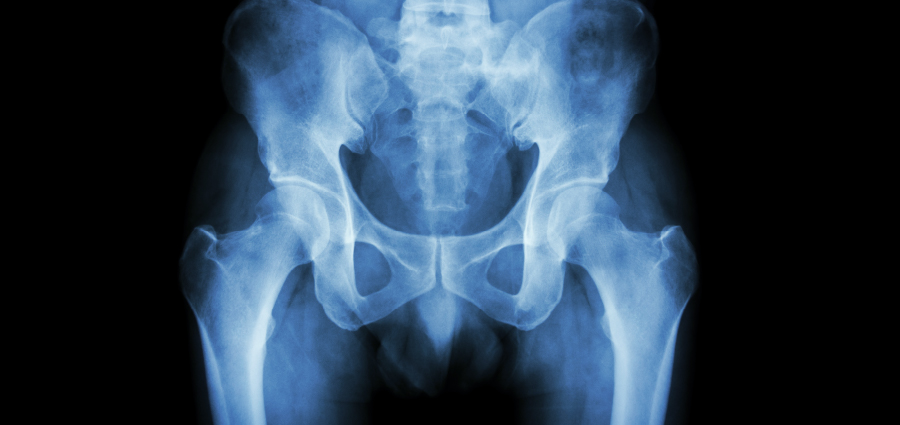

Many forms of arthritis and related conditions can cause pain, stiffness and swelling in the hips. Hip pain can occur on the outside or inside of the hip, the upper thigh or outer buttock. Here are some diseases that can affect the hips.

Osteoarthritis (OA) is the most common form of arthritis. Previously known as “wear and tear” arthritis, OA is a disease of the joint that causes inflammation and damage to the tissues in the joint, including cartilage, which cushions the ends of the bones where they meet to form joints. The result is stiffness, pain, loss of movement and the formation of bony growths (bone spurs). Pain from hip OA is often felt in the groin area and front of the thigh. Stiffness may be worst after periods of inactivity, like first thing in the morning.

Rheumatoid arthritis (RA) is a chronic inflammatory disease that occurs when the immune system doesn’t work properly and attacks the body's own tissues, including the joints. Hip involvement in RA is often signaled by pain, stiffness or swelling in the hips, thighs or groin area. RA usually affects the same joint on both sides of the body, such as both hips.

Axial spondyloarthritis (axSpA) causes inflammation of the spine, running from the neck to the lower back, and especially the joints that connect the spine and the hips, called the sacroiliac joints. It can lead to fusion of the vertebrae, chronic pain and stiffening in the back, hips and ribs.